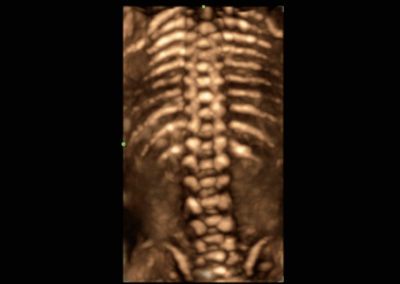

NueWa i9

El Nuewa I9, diseñado exclusivamente para mujeres y atención médica neonatal, brinda una experiencia innovadora integral. Estas innovaciones se desarrollan sobre la base de conocimientos profundos en escenarios clínicos complejos, para proporcionar respuestas precisas y oportunas, una gran eficiencia y una experiencia de usuario extraordinaria. •

- Diseño del panel de control inteligente y específico para exámenes clínicos con teclas especiales de tinta electrónica

- Diseño innovador con diseño adaptable para diferentes situaciones clínicas